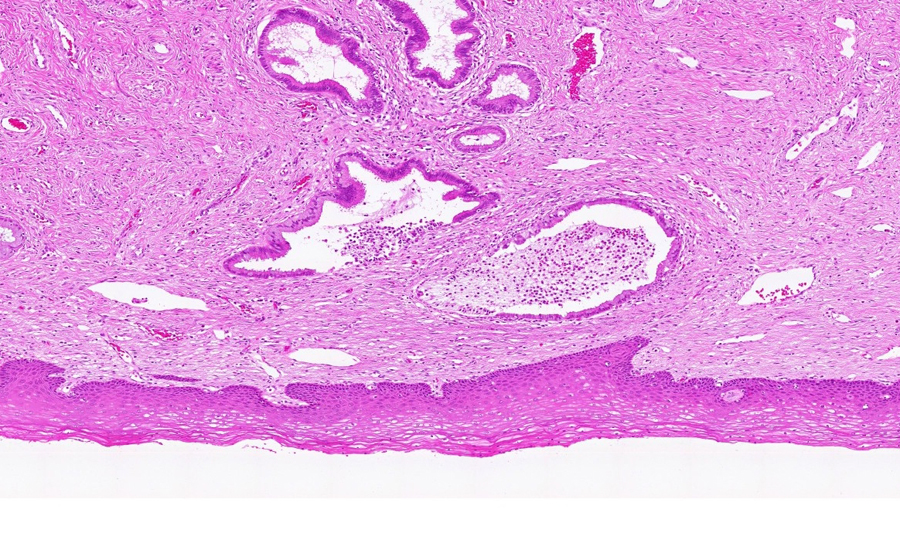

Image 1 - 3.1X

Slide 3 - Image 1